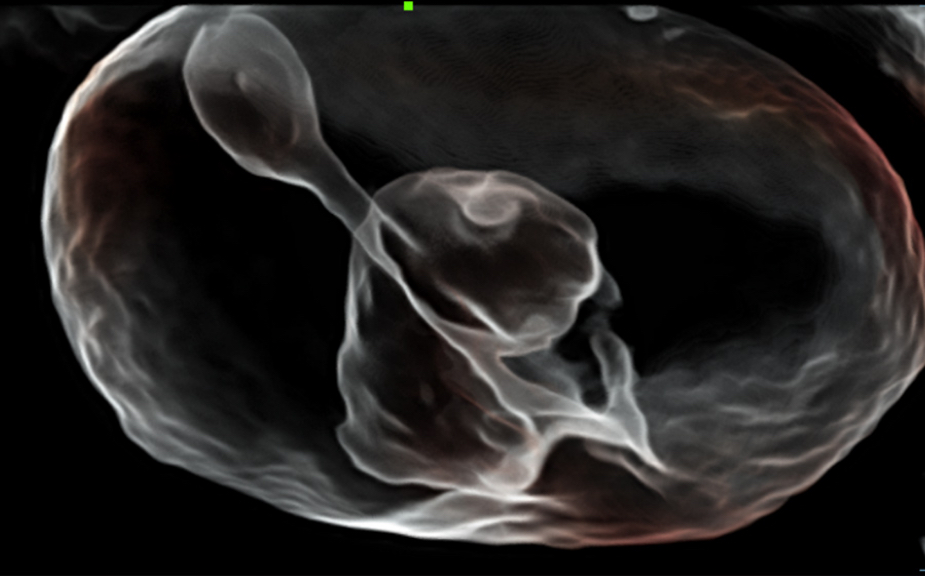

El sistema Nuewa I9, dise?ado exclusivamente para la atenciĂłn mĂ©dica neonatal y de mujeres, brinda una experiencia innovadora integral. Estas innovaciones se desarrollan sobre la base de un conocimiento profundo de situaciones clĂnicas complejas para proporcionar respuestas precisas y oportunas, una gran eficiencia y una experiencia de usuario extraordinaria.

La plataforma ZST+?es una innovaciĂłn extraordinaria que representa toda una evoluciĂłn en el ĂĄmbito de la ecografĂa. Transforma las mĂ©tricas ecogrĂĄficas de la formaciĂłn de haces convencional al procesamiento basado en datos de canal. Supera la limitaciĂłn tradicional de tener que equilibrar entre resoluciĂłn espacial, resoluciĂłn temporal y uniformidad del tejido, con lo que ofrece una calidad de imagen excepcional para soluciones de producciĂłn de imĂĄgenes infinitas con mejoras continuas.